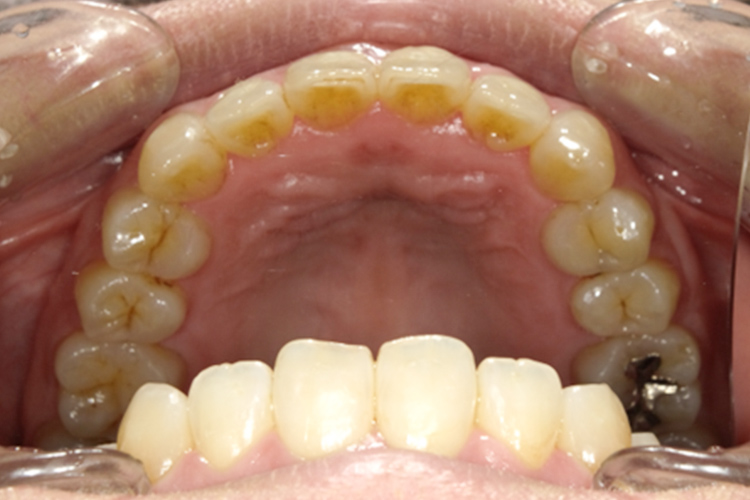

治療前

治療後